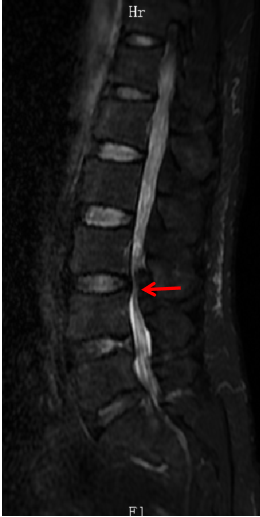

经腰椎磁共振检查结果显示,陶先生黄韧带肥厚并椎管狭窄,马尾神经冗余,属于腰椎管狭窄症再度复发。

箭头所指为陶先生腰3-4间隙水平狭窄严重, 上方马尾神经迂曲